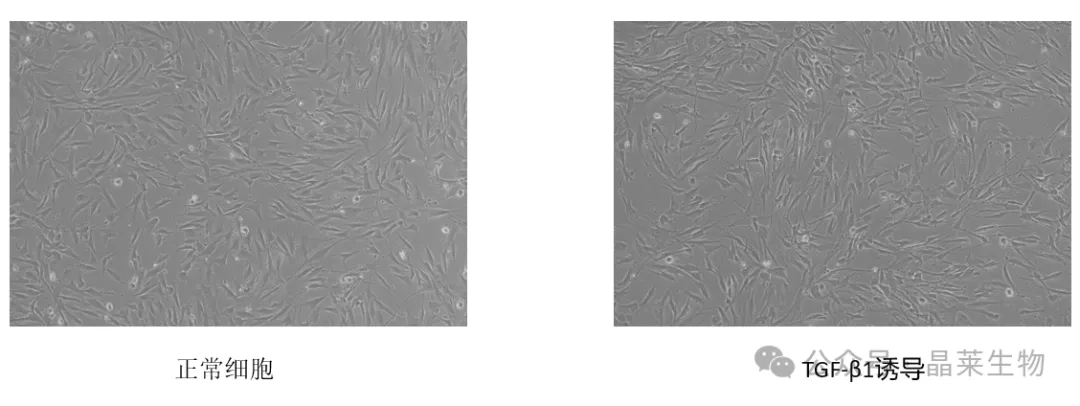

① 光学显微镜观察成纤维细胞形态变化;

1. 显微镜下可观察TGF-β1诱导人正常肝成纤维细胞活化的形态变化和细胞增殖情况;